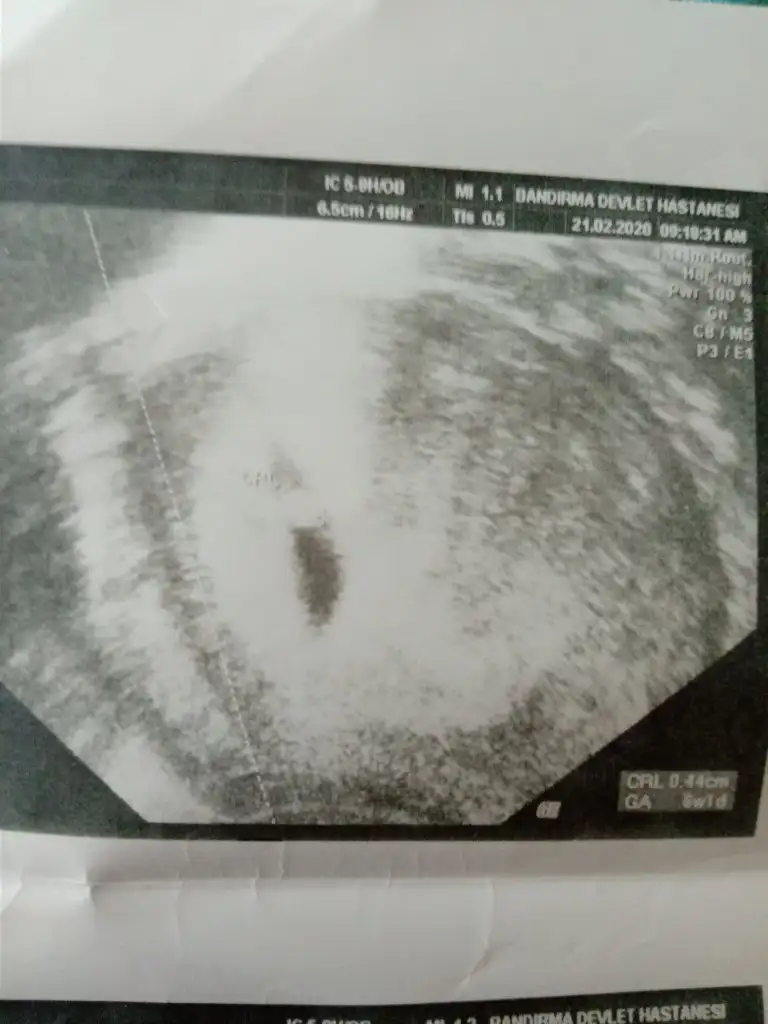

Teşekkür ederim ben sizin sandım herkes siiz etiketleyince 🙈 6 haftalık olan vajinal ultrason ve bebek çok ortada duruyor ondan atmadım. Sağolun Bakalım 10 gün sonra söylerse yazicam sizede ❤❤

paylaşın bebege değil yolksac bakılıyor 😊